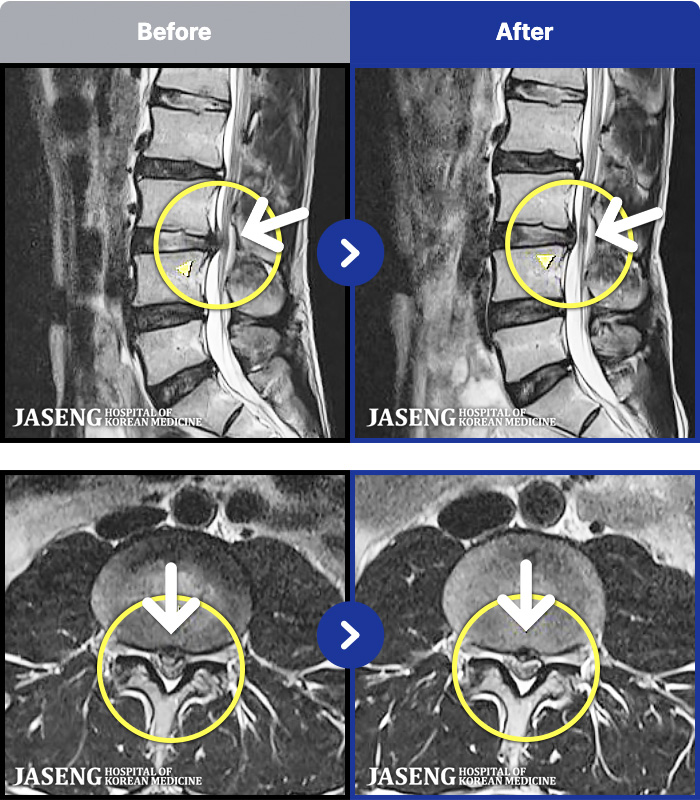

1,298 MRI ũ ʸ Ȯϼ.